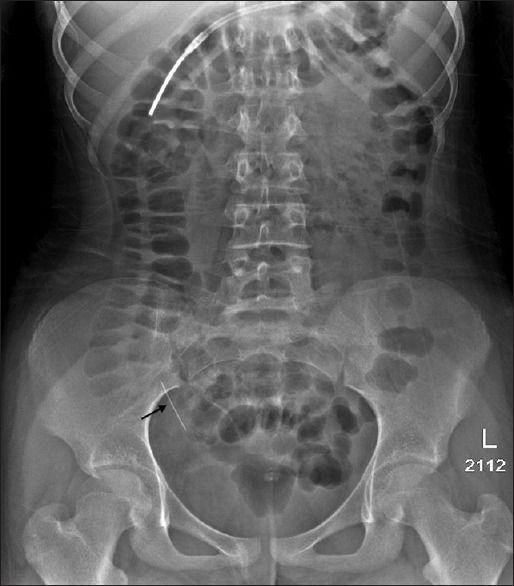

В публикации[1] доктора из Саудовской Аравии представлен опыт диагностики и лечения 13-летней пациентки, которая была госпитализирована через 48 часов после того, как случайно проглотила булавку для платка. Она жаловалась на жар и умеренную боль в животе, тошноту. При обследовании зафиксированы: температура тела — 38,6 °С, артериальное давление — 102/60 мм рт. ст., частота сердечных сокращений в покое — 118 ударов в минуту, частота дыхания — 20 дыхательных движений в минуту. При пальпации живот мягкий, не напряжен. Результаты анализа крови: гемоглобин — 125 г/л, лейкоциты — 7,4 × 109 клеток/л. При рентгенографии органов брюшной полости в тонкой кишке обнаружена булавка, это подтвердила и КТ живота (рис. 1). В ходе динамического наблюдения отмечено продвижение булавки в толстую кишку (рис. 2). В течение 4 дней, пока ИТ оставалось в восходящей ободочной кишке, пациентка продолжала жаловаться на боли в животе. В связи с этим ей была назначена колоноскопия, которая обнаружила булавку в восходящей ободочной кишке, в нескольких сантиметрах от слепой кишки. Повреждений слизистой оболочки зафиксировано не было, булавка была успешно извлечена с помощью щипцов «крысиный зуб» (рис. 3).

Рисунок 1.